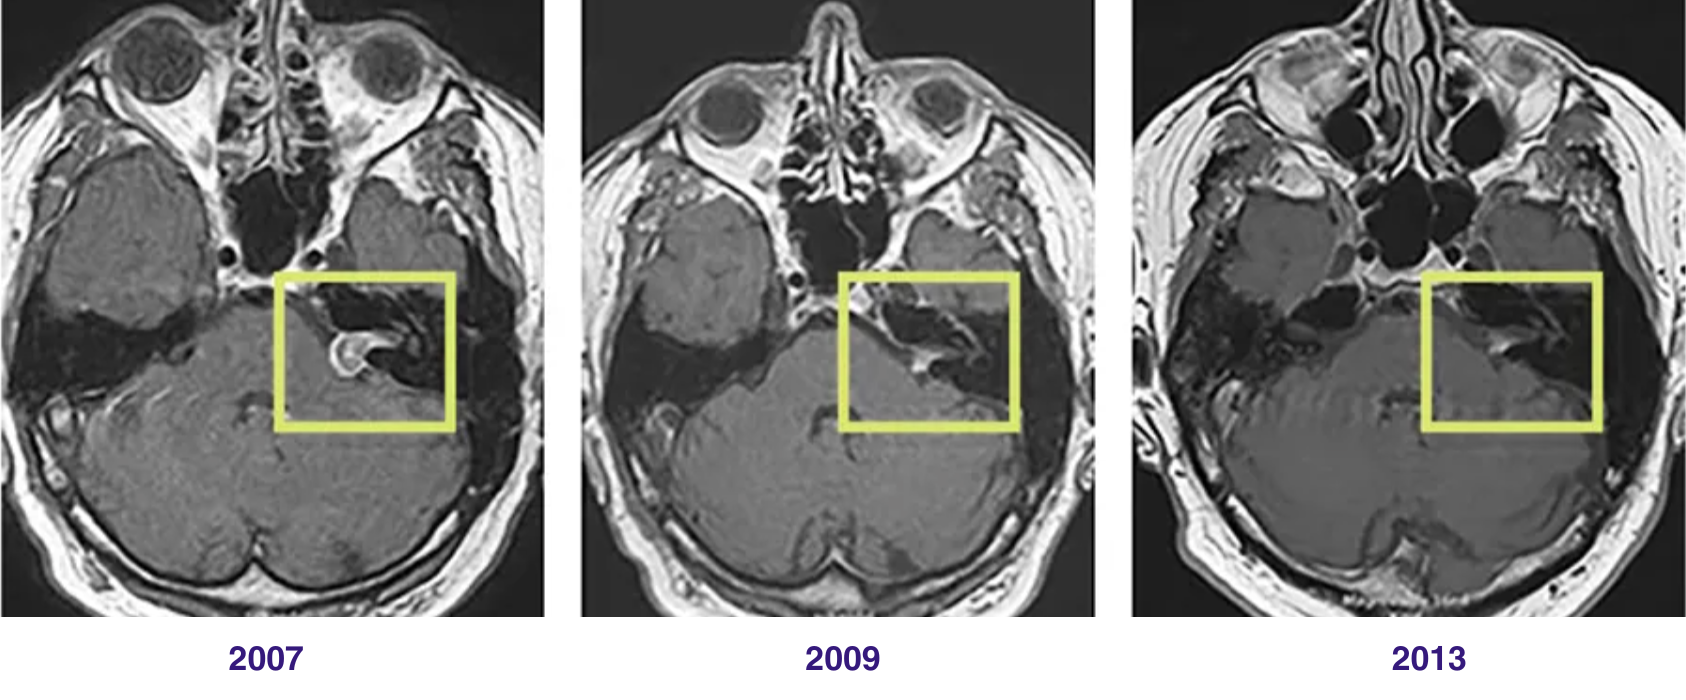

Beispiel einer CyberKnife-Therapie des Akustikusneurinoms im 6-Jahres-Verlauf

Die robotergeführte, radiochirurgische Behandlung hat den Effekt, dass Tumorzellen im Zeitverlauf absterben können. Im MRT ist das gut sichtbar: Im dargestellten Fall konnte mithilfe der CyberKnife-Therapie (2007) nicht nur das Tumorwachstum gestoppt werden, das Akustikusneurinom ist mit der Zeit auch deutlich geschrumpft (Bild Mitte 2009) und im weiteren Verlauf (2013) kaum noch zu sehen (rechts).